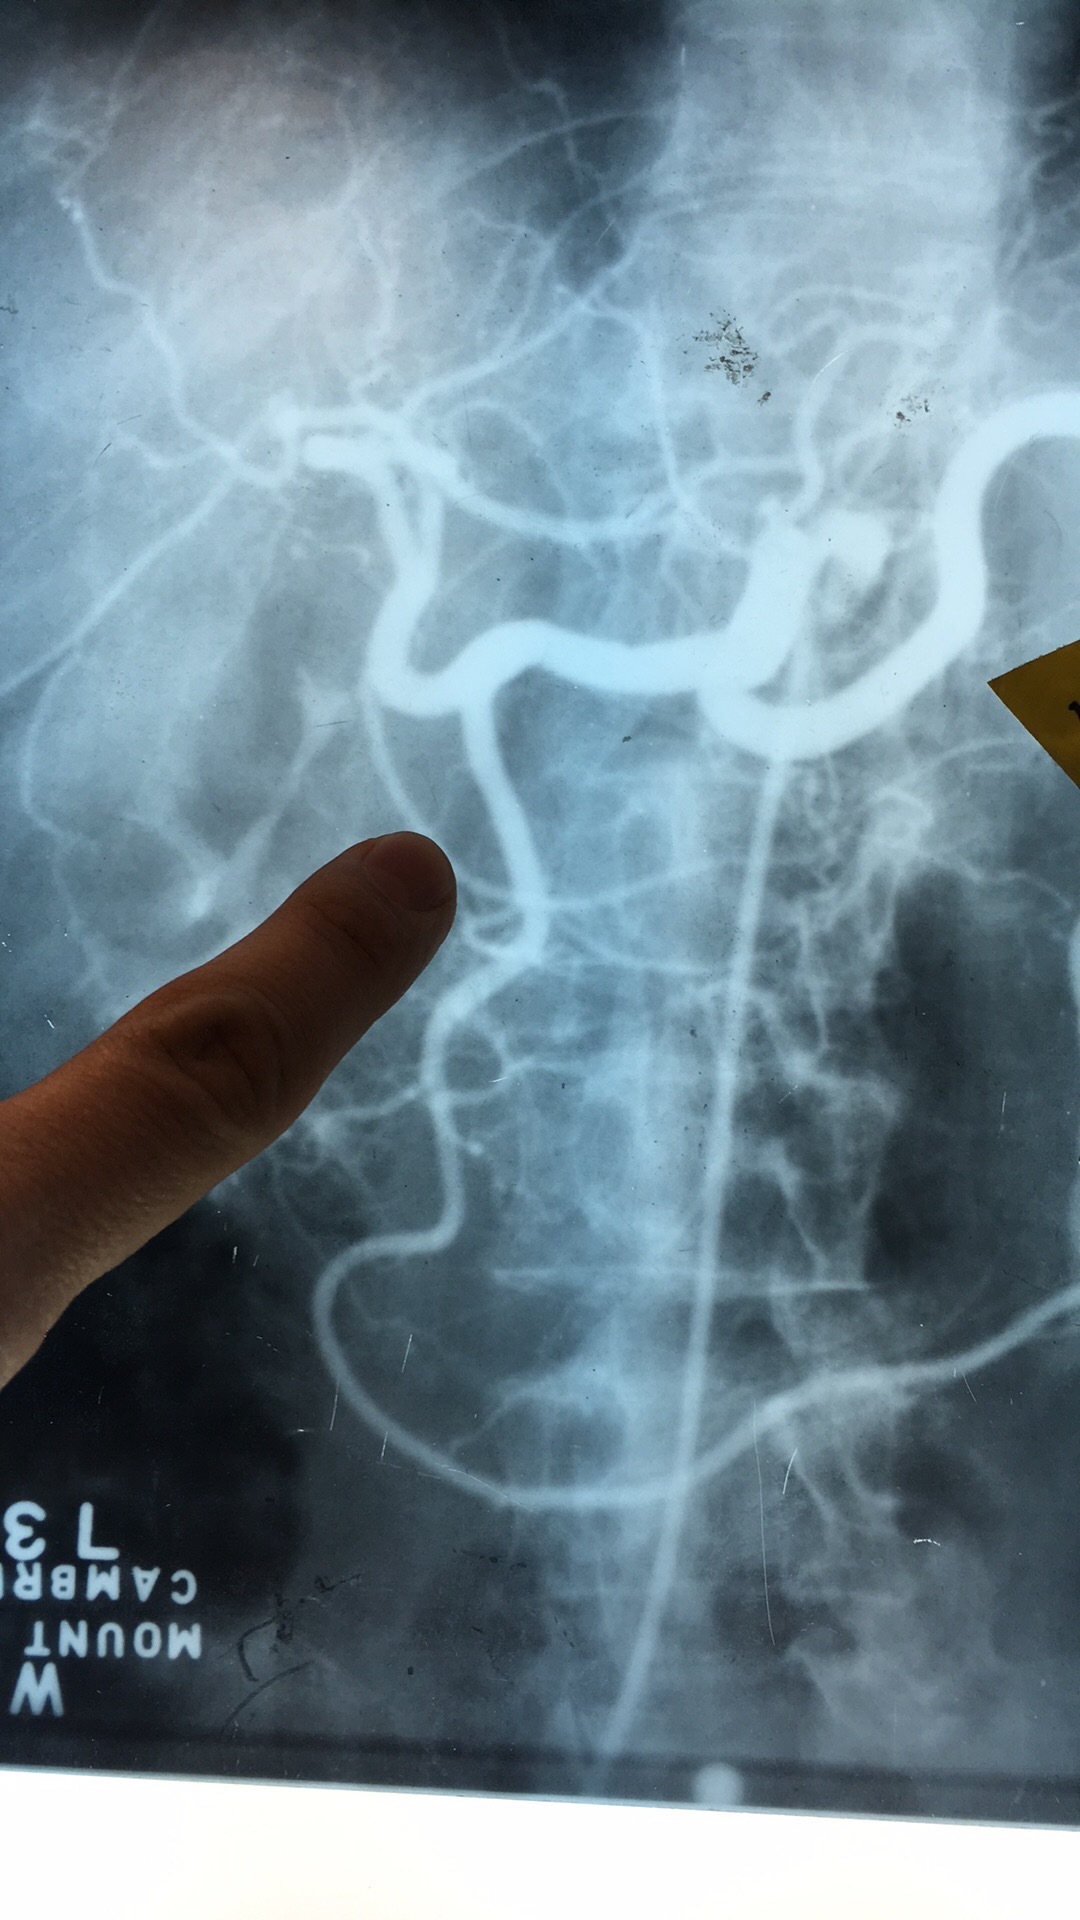

What artery? What comes off it?

Celiac Trunk. Left Gastric Art, Splenic Artery, Common Hepatic Artery